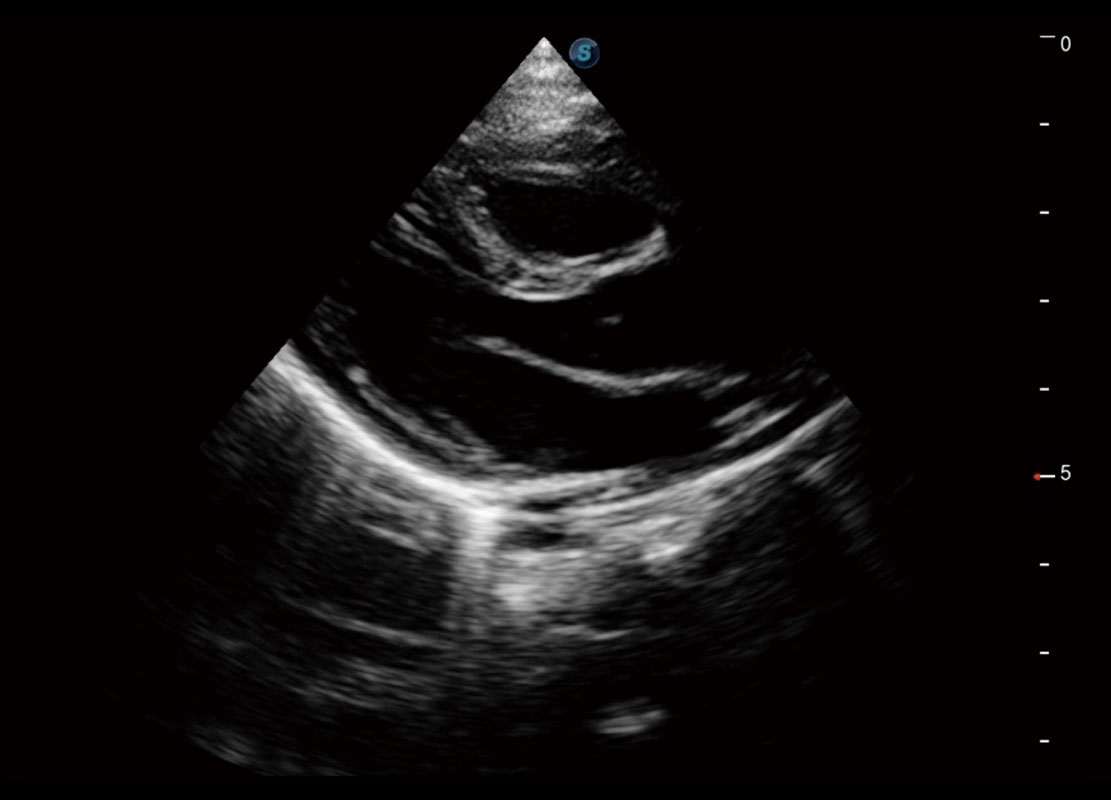

• 四腔切面

• 四腔心血流

• 右室双出口

• 胎心容积成像